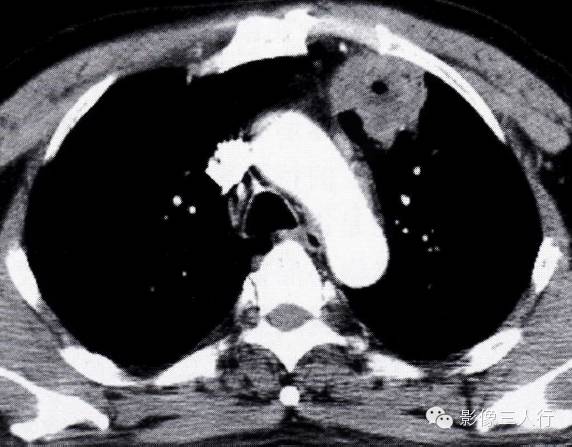

(4)周围模糊:相邻肺内有长条束状影,部分边缘模糊(图2-20,图2-21)。

图2-20纵隔旁脓肿肺窗表现 病灶与纵隔接触面宽,周围有斑片状模糊影